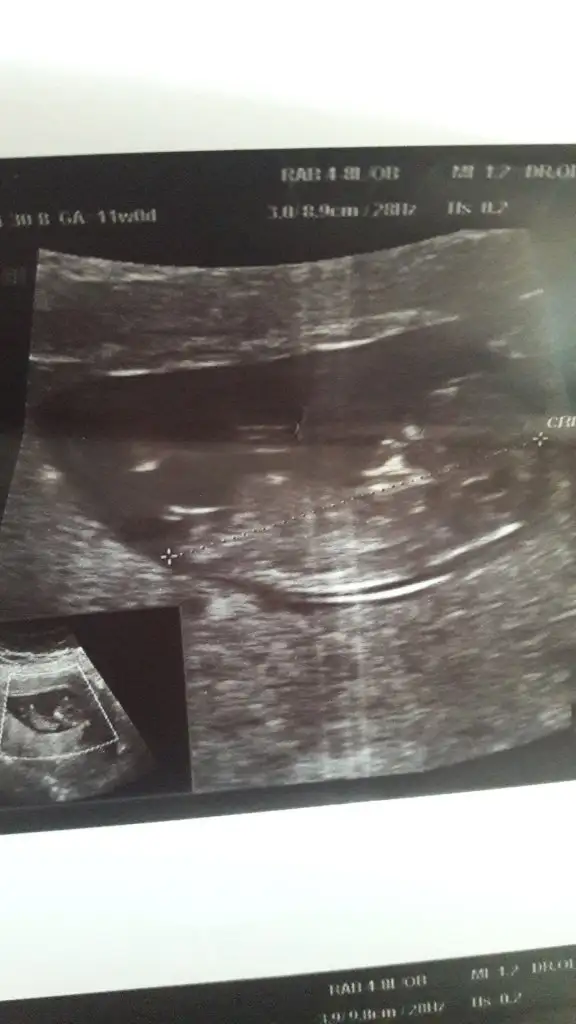

Canım bizede 12+5 de tahminde bulunurmusun karından usd dr bir tahminde bulundu ama net değil dedi🤗

• image.webp

image.webp

17,9 KB · Görüntüleme: 68

Merhaba yukarıda sanırım arada gözden kaçtı tica etsem banada yorum yaparmısınız 12+5 karından usg🤗

Eklentiler